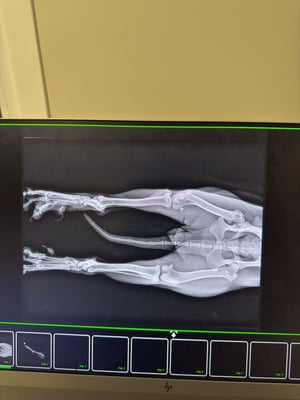

Genau so wurde diese etwa 5-jährige Hündin gefunden: von einem Auto angefahren und mit Schmerzen zurückgelassen. Denn es blieben Verletzungen an ihren Hinterbeinen zurück, die dringend versorgt werden mussten.  Niemand suchte nach ihr. Niemand fragte nach ihr. Niemand wartete irgendwo auf sie. Doch sie war nicht vollständig allein – ihre Schwester Kaja wich ihr nicht von der Seite.

Ihr Verletzungen an den Hinterbeinen sind sehr schön verheilt, zurück bleiben nur Narben.

That's exactly how this approximately 5-year-old dog was found: hit by a car and left for dead in pain. Injuries to her hind legs required urgent medical attention. No one came looking for her. No one asked about her. No one was waiting for her anywhere. But she wasn't completely alone – her sister Kaja stayed by her side.

Her injuries to her hind legs have healed beautifully, leaving only scars.